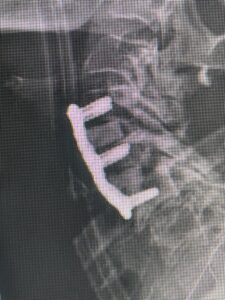

This 59 year-old female had severe bilateral leg pain and numbness over a 6 month period. The patient had failed conservative treatment with physical therapy, chiropractic care, and medications. MRI revealed that she had severe lumbar stenosis with a grade 1 spondylolisthesis or “slipped disc” at L5-S1 (Fig 2).

In addition, she had previously undergone both front and back surgery for severe cervical stenosis where her posterior hardware had failed because of her severe osteoporosis requiring us to remove the posterior hardware . This required her to have an anterior or front operation which allowed better fixation to her spine because of the load-sharing nature of the interbody grafts in addition to her anterior cervical plate (Fig 3).

(Fig 3) Lateral Intraoperative Cervical X-ray demonstrating good alignment after C4-C6 anterior cervical discectomy and interbody fusion with plate. Note the interbody grafts help load share the plate in this patient with severe osteoporosis.